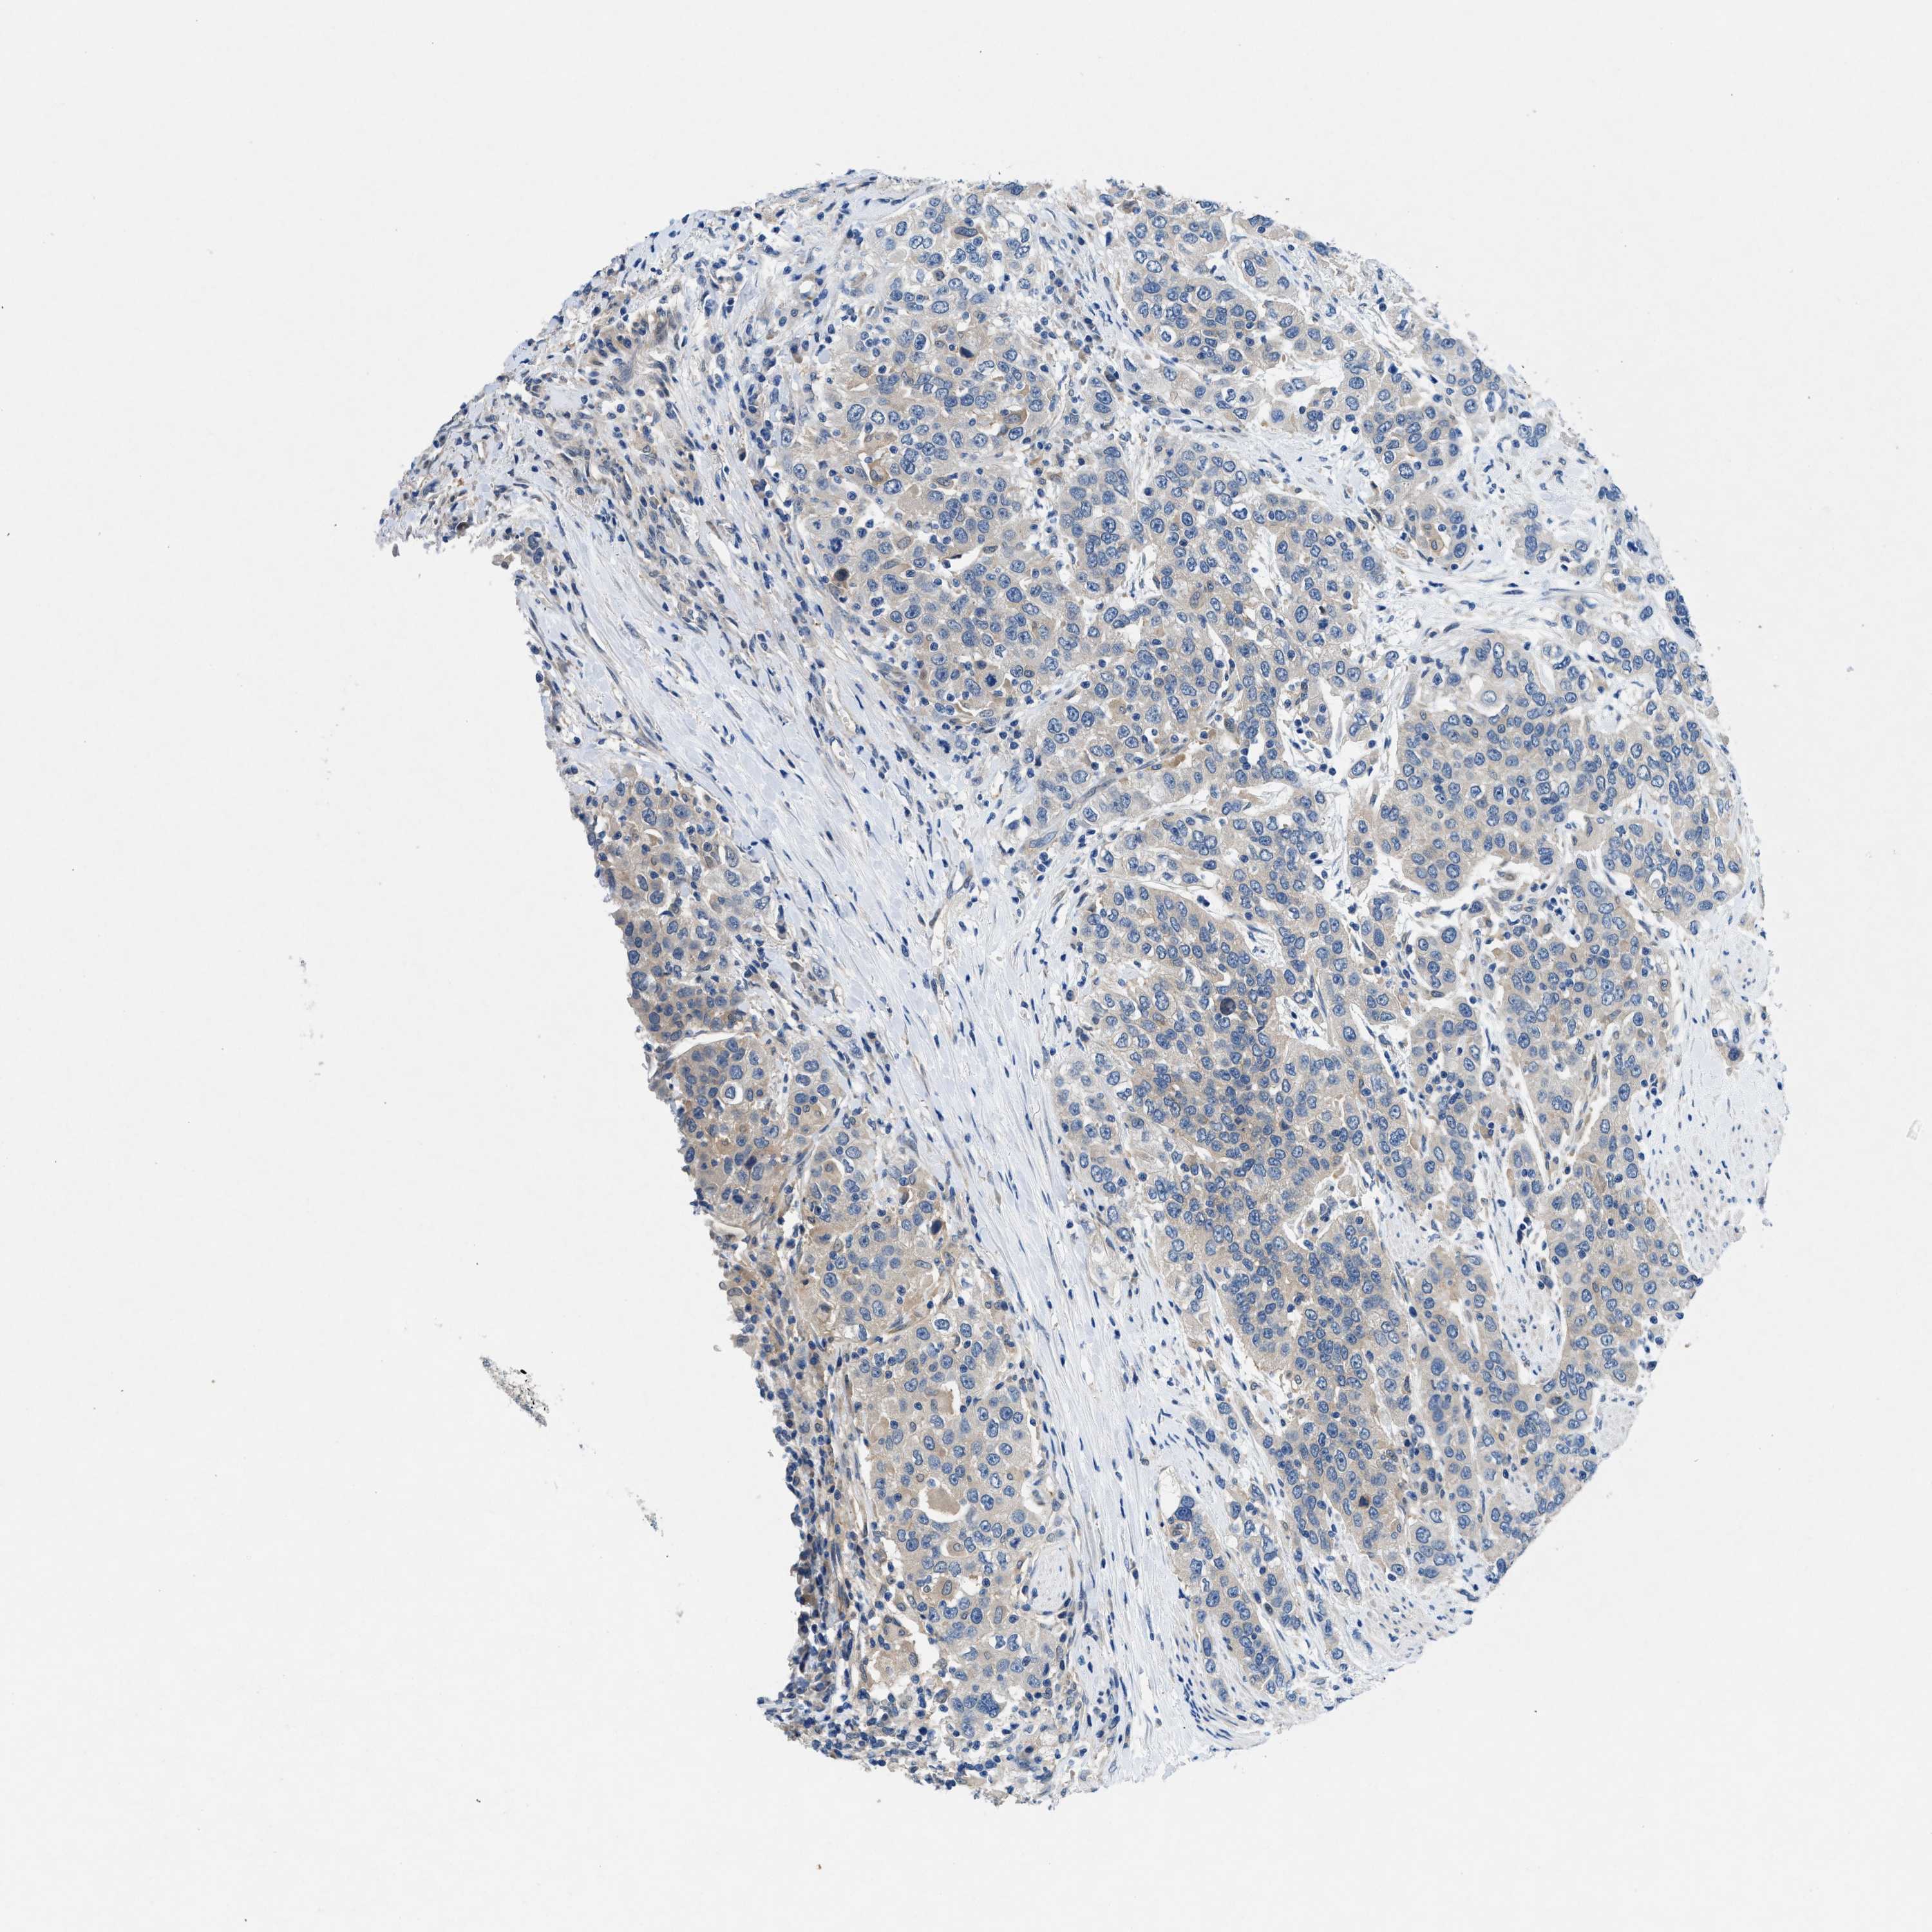

UROTHELIAL CANCER - Protein expressioni

A mouse-over function shows sample information and annotation data. Click on an image to view it in a full screen mode. Samples can be filtered based on level of antibody staining by selecting one or several of the following categories: high, medium, low and not detected. The assay and annotation is described here.

Antibody stainingi

Antibody staining in the annotated cell types in the current human tissue is reported as not detected, low, medium, or high, based on conventional immunohistochemistry profiling in selected tissues. This score is based on the combination of the staining intensity and fraction of stained cells.

Each image is clickable and will lead to virtual microscopy that enables deeper exploration of all samples and also displays staining intensity scores, fraction scores and subcellular localization as well as patient and tissue information for each sample.

Antibody HPA018271

Urothelial carcinoma, Low grade

Urothelial carcinoma, High grade